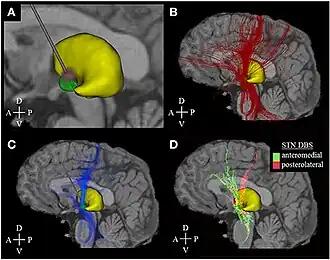

DBS is used to manage Parkinson's disease symptoms that are resistant to medication.[20][30] The ideal candidate for DBS is one that does not have dementia, is not severely depressed, and who does not have falls while being in their best on-drug state, but who do have disabling motor fluctuations or dyskinesias that necessitate bilateral surgery.[1] It is treated by applying high-frequency (> 100 Hz) stimulation to target structures in the deep subcortical white matter of the basal ganglia. Frequently used targets include the subthalamic nucleus (STN), globus pallidus internus (GPi) and ventrointermediate nucleus of the thalamus (VIM). Neurostimulation can be considered for people who have Parkinson's with motor fluctuations and tremors inadequately controlled by medication, or to those who are intolerant to medication as long as they do not have severe neuropsychiatric problems.[31] A >30% degree of symptom responsiveness to dopamine is a strong predictor of a good response to DBS surgery, though it is not mandatory. This has led most centers to require evaluation both on and off dopamine prior to the procedure to increase the likelihood of success.[32] DBS is not currently considered to be a disease-modifying treatment.[33] Shorter disease duration pre-operatively tends to lead to better results after surgery. The response from DBS is only as good as the patient's best "on" time, with the exception of tremor, which may show greater improvement than that seen with medication.[34]

Frequencies above 100 Hz are most effective for cessation of tremor, while lower frequencies have less effect.[107] In clinical practice, frequencies between 80 and 180 Hz are typically applied. DBS electrodes commonly target the ventrointermediate nucleus of the thalamus (VIM) or ventrally adjacent areas in the zona incerta or posterior thalamus. Multiple targets along the circuitry of the cerebellothalamic pathway (also referred to as the dentatorubrothalamic or dentatothalamic tract) have been shown to have similar therapeutic effect.[108][109][110]